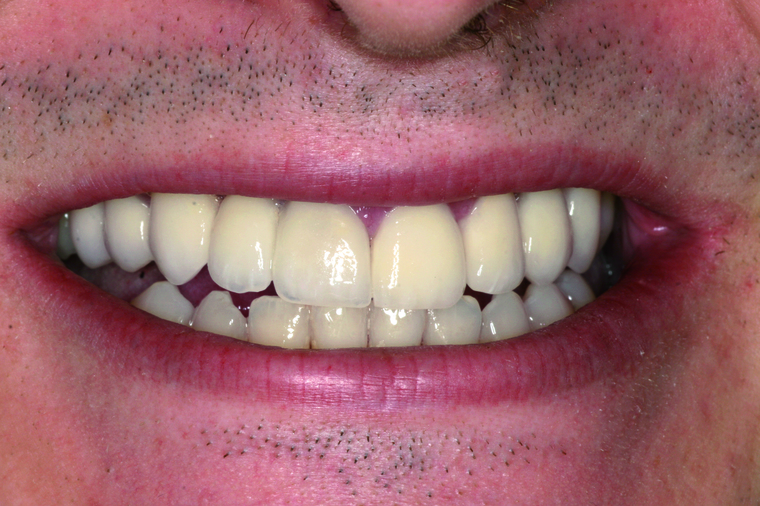

Generalsanierung

Viele Kunden die zu uns nach Salzburg kommen benötigen eine Generalsanierung der Zähne. Gründe dafür sind Zahnarztangst, Zeitmangel und schlechte Erfahrungen in der Kindheit. Unser Konzept ist genau auf diese umfangreichen Fälle abgestimmt:

Bei einer Generalsanierung müssen alle zahnmedizinischen Bereich in Betracht gezogen werden, dies beginnt bei der Aufklärung und Prophylaxe, gefolgt von Zahnfleischbehandlungen und Kariestherapie, eventuellen Zahnentfernungen, Knochenaufbauten und wird durch ästhetischen Zahnersatz abgeschlossen. Unser Recall-System hält die erreichte Zahnsanierung über lange Jahre stabil.